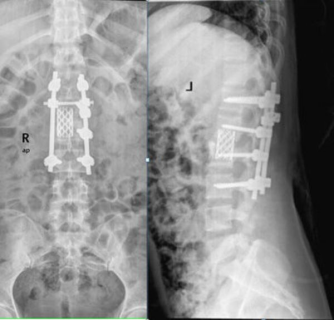

C:\Users\ADMINI~1\AppData\Local\Temp\ksohtml5168\wps28.png

脊柱结核术后X线